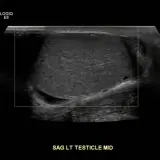

Over 2,100 interactive radiology cases, curated by radiologists for your level of training. Scroll, window, and view cases full screen — just like on PACS. Click linked findings in each writeup to jump straight to them on the image. Cases include sample reports, a focused discussion section, original illustrations, and videos.

PACSで期待されるツールを完備した完全インタラクティブな症例 — スクロール、ウィンドウ調整、ズーム、パン、計測、ROI、フルスクリーンモード。

重要な所見を症例画像上に直接ハイライトする豊富なアノテーション。症例解説内のリンクされた所見をクリックすると、スキャン上の正確な位置へジャンプできます。